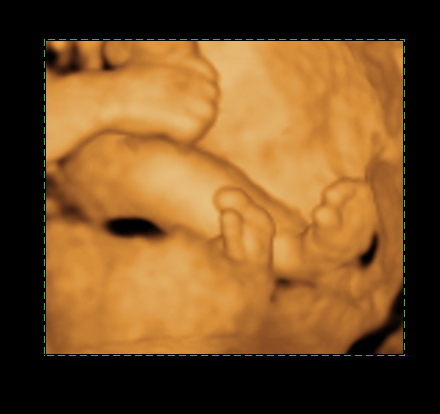

En pont ma toltottem be a 24.hetet,es mar tudjuk hogy kisfiu lesz!

A Botond nevet valasztottuk.